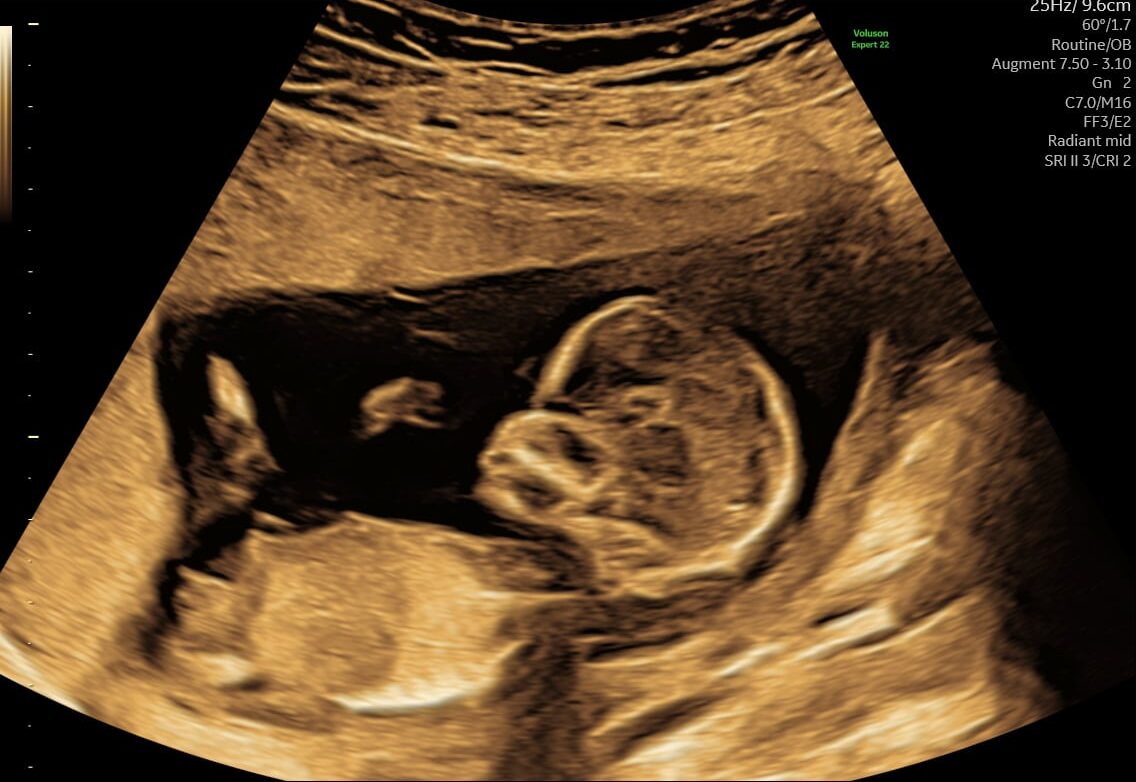

(11+0 til 11+6)

I uge 12 fortsætter den lille med at vokse og udvikle sig hurtigt. Fosteret er nu omkring 5-6 cm langt og vejer cirka 14 gram. Her er nogle af de vigtige udviklinger, der sker i denne uge:

- Ansigtstræk: Fosterets ansigt bliver endnu mere udtalt. Øjnene bevæger sig tættere mod forsiden af ansigtet, og ørerne er næsten på deres endelige placering.

- Lemmer: Arme og ben fortsætter med at forlænge sig og bliver mere proportionale med kroppen. Fingre og tæer er tydeligt adskilte, og negle begynder at dannes.

- Indre Organer: Alle vigtige organer er dannet og begynder at fungere. Fordøjelsessystemet træner bevægelser, og nyrerne begynder at producere urin.

- Hjertet: Hjertet slår kraftigt og regelmæssigt med en hastighed på omkring 120-160 slag per minut. Det pumper blod gennem hele kroppen.

- Knogleudvikling: Brusk fortsætter med at blive omdannet til knoglevæv, hvilket styrker skeletstrukturen. Ribbenene begynder at blive synlige.

- Reflekser: Fosteret begynder at udvikle reflekser. Hvis du rører ved din mave, kan fosteret reagere på stimuli ved at bevæge sig.